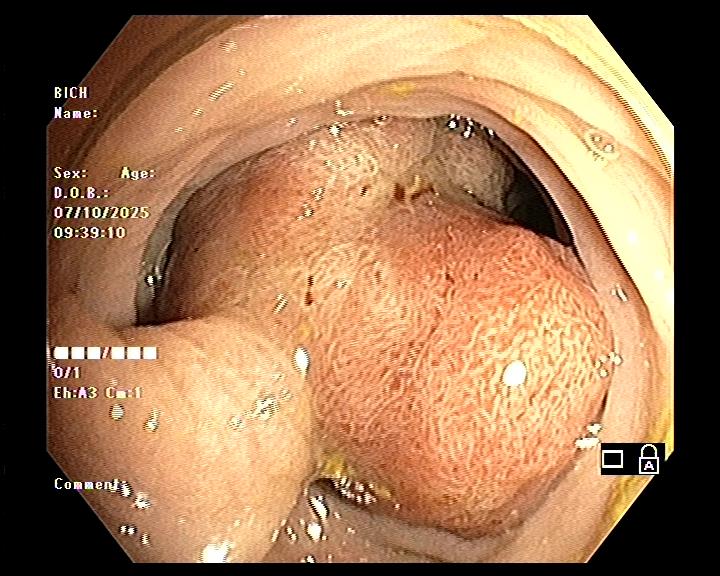

- Trên nội soi: polyp thường có hình chùm nho, niêm mạc nhẵn, dễ chảy máu.

Polyp Peutz–Jeghers là dạng polyp hamartomatous, cấu trúc mô học gồm các tuyến ruột được bao quanh bởi các bó cơ trơn phát triển bất thường.

- Sự xuất hiện của polyp hamartomatous (polyp mô thừa lành tính) trong đường tiêu hóa – đặc biệt ở ruột non, dạ dày, đại tràng.